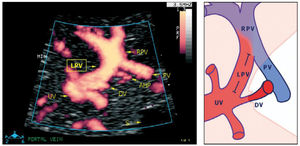

The left portal branch deserves a particular focus as it serves as a watershed area between the umbilical and splanchnic venous supply to the fetal liver (Figure 9)31–33. Thus, it has the potential of gauging an imbalance associated with fetal growth-restriction23, DM28, twin-twin transfusion syndrome, fetal liver diseases or anomalies of the abdominal venous system34,35.

The left portal vein (PV) directs umbilical flow beyond the ductus venosus (DV) towards the right side to the junction with the portal stem, or the main portal vein (PV), where umbilical blood blends in with low-oxygenated splanchnic blood and enters the right portal branch and liver lobe. LPV constitutes a watershed area where blood may even reverse to feed splanchnic blood into the umbilical vein and ductus venosus when perfusion pressure in the umbilical vein is low. After birth when the umbilical vein obliterates, the velocity is permanently reversed, and the portal stem circulates both right and left liver lobes. S, spine; UV, intra-abdominal umbilical vein; V, stomach33.

The intra-abdominal umbilical vein, half embedded in the caudal surface of the fetal liver, feeds the portal branches of the left liver lobe as it heads towards the ductus venosus inlet. Here the umbilical venous flow turns right following the left portal branch to join with the main portal stem and the right portal branch (Figure 10).

Details of the left portal vein connections visualized using power Doppler sonography

A magnified sketch (right panel) clarifies the details. The site for Doppler recording of the LPV would be the section between the istmus of the ductus venosus (DV) and the junction with the portal vein (PV) and the right portal vein (RPV). The insonation should be aligned and the sample volume reduced to 2-3mm to minimize interference. AHP, arteria hepatica; S, stomach; UV, umbilical vein33.

There has been some discussion of the nomenclature of this venous section, i.e., whether to name according to prenatal developmental origin, postnatal anatomic naming traditions or current clinical needs of simplicity36. The section between the ductus venosus inlet and the junction with the portal stem is, for simplicity reasons, called the ‘left portal vein’ (Figure 9), also known as the transverse sinus, or portal sinus, particularly when including the somewhat wider portion in front of the ductus venosus inlet. It is readily accessible in a modified transverse scan of the fetal abdomen tilted slightly caudally (Figure 11). The Doppler recording achieves a complete alignment when interrogating at 30–60° to the sagittal plane. The sample volume should be reduced to 2–3mm to avoid interference from the umbilical vein, ductus venosus, portal stem or right portal branch.